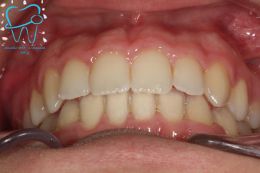

1982 visualizzazioni Una paziente di 12 anni si presenta alla nostra osservazione con una malocclusione in arcata superiore ed inferiore. La situazione appare complicata, oltre che da un affollamento notevole in arcata superiore, dalla agenesia dell'elemento 4.5 e con il 3.6 molto distrutto e difficilmente recuperabile per il futuro in maniera pervedibile. Si decide a questo punto per un trattamento ortodontico fisso con il movimento mesiale degli elementi posteriori e la chiusura degli spazi solo con denti sani e pienamente funzionanti ed evitare successivamente costosi procedimenti protesici.